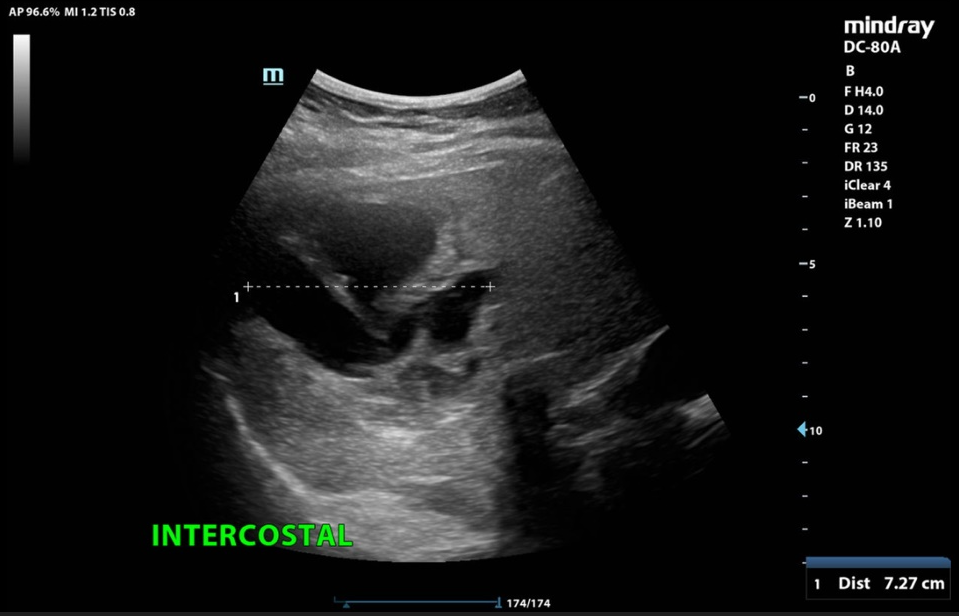

In der klinischen Untersuchung zeigt sich ein diskreter Sklerenikterus und ein leichter rechtsseitiger Oberbauchschmerz. Laborchemisch zeigen sich erhöhte Transaminasen sowie eine Bilirubinämie. Die Leukozyten und das C-reaktive Protein waren ebenfalls erhöht. In der orientierenden Sonographie bei dem Internisten zeigte sich eine ca. 16 cm messende echoarme, septierte Raumforderung, woraufhin die Patientin zur stationären Abklärung eingewiesen wurde. Bei der Aufnahme wurde eine Computertomographie des Abdomens durchgeführt.

In der CT-Untersuchung zeigte sich eine 16 x 14 cm messende, multilobulierte hypodense Raumforderung in den Lebersegmenten VII, VIII und VIa mit konsekutiver Cholestase im rechten Leberlappen. Die Pfortader und die Lebervenen waren offen. Die restlichen Organe waren unauffällig. Bei komplizierten Leberzysten wurde die Serologie für Echinokokkose abgenommen. Auf die gezielte Frage nach Kontakt zu Hunden und Füchsen hat Frau K. angegeben, dass sie drei Hunde auf dem Bauernhof hat. Der Echinokokken-IgG-Screening-ELISA war mit 47 U/ml positiv. Somit wurde die Diagnose einer Echinokokkose gestellt.